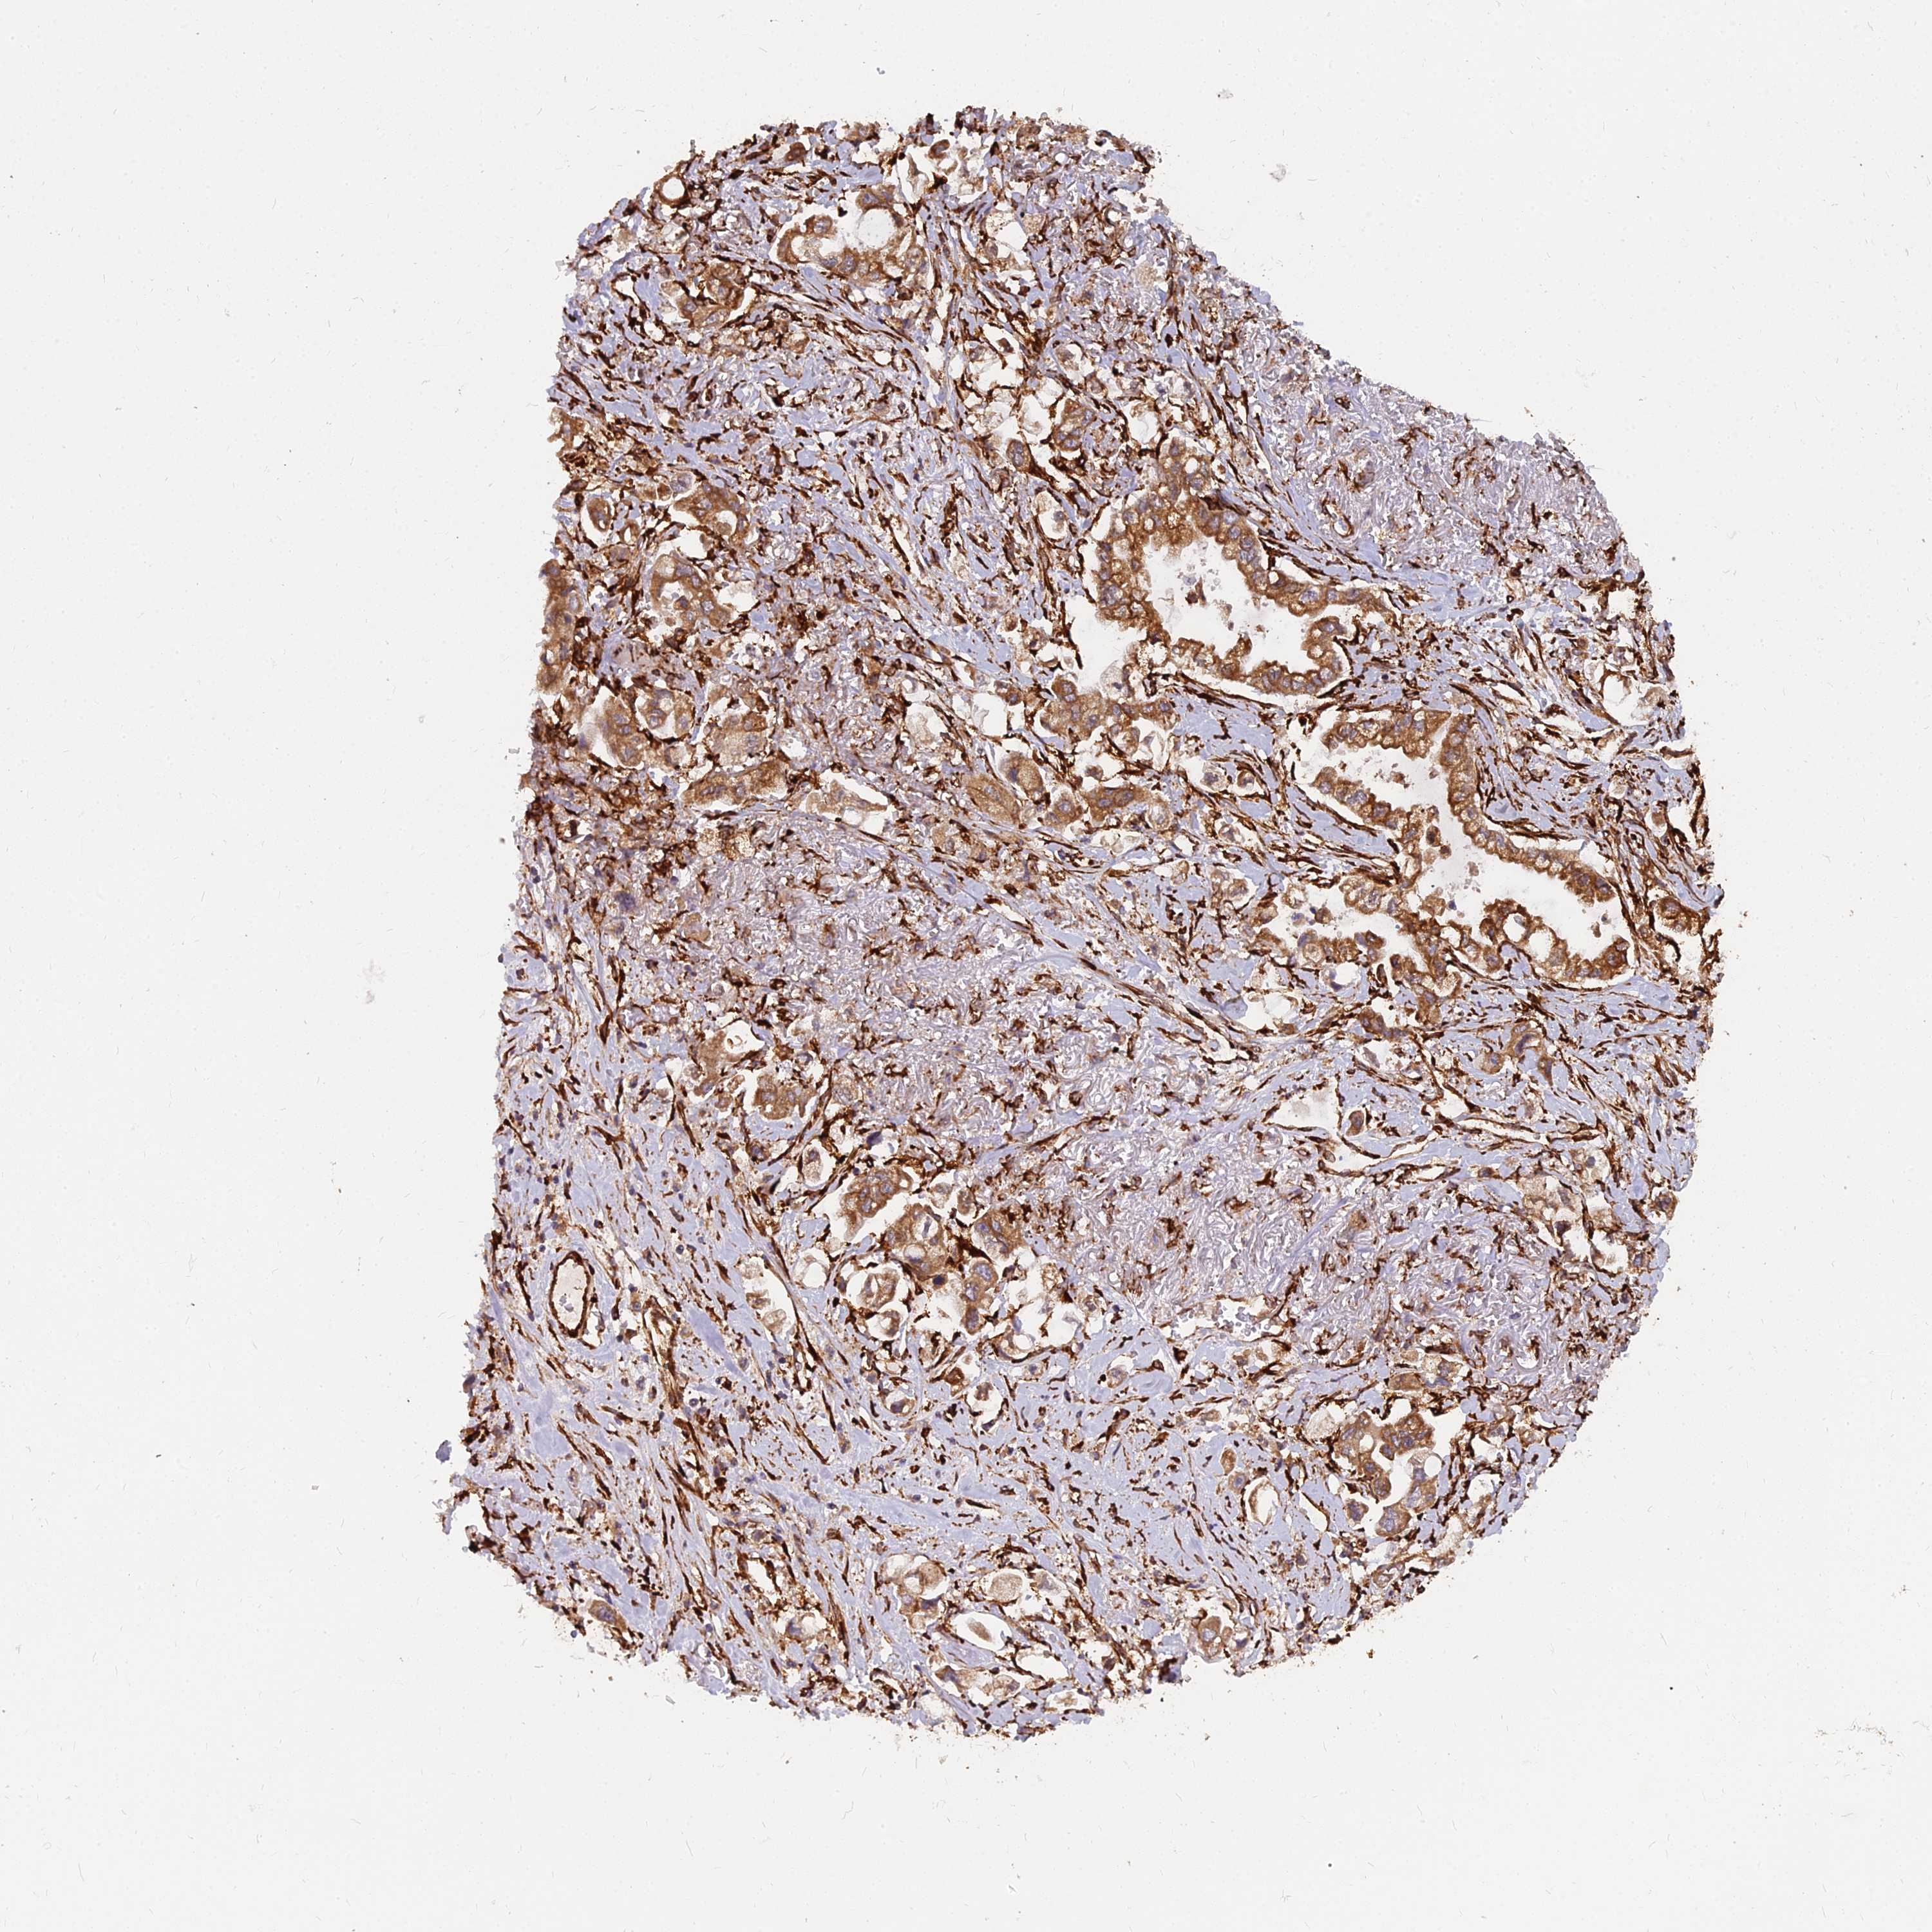

STOMACH CANCER - Protein expressioni

A mouse-over function shows sample information and annotation data. Click on an image to view it in a full screen mode. Samples can be filtered based on level of antibody staining by selecting one or several of the following categories: high, medium, low and not detected. The assay and annotation is described here.

Note that samples used for immunohistochemistry by the Human Protein Atlas do not correspond to samples in the TCGA dataset.

Antibody stainingi

Antibody staining in the annotated cell types in the current human tissue is reported as not detected, low, medium, or high, based on conventional immunohistochemistry profiling in selected tissues. This score is based on the combination of the staining intensity and fraction of stained cells.

Each image is clickable and will lead to virtual microscopy that enables deeper exploration of all samples and also displays staining intensity scores, fraction scores and subcellular localization as well as patient and tissue information for each sample.

Antibody HPA045217

Staining

High

Medium

Low

Not detected

Intensity

Strong

Moderate

Weak

Negative

Quantity

>75%

75%-25%

<25%

None

Location

Nuclear

Cytoplasmic/membranous

Cytoplasmic/membranous,nuclear

Adenocarcinoma, NOS